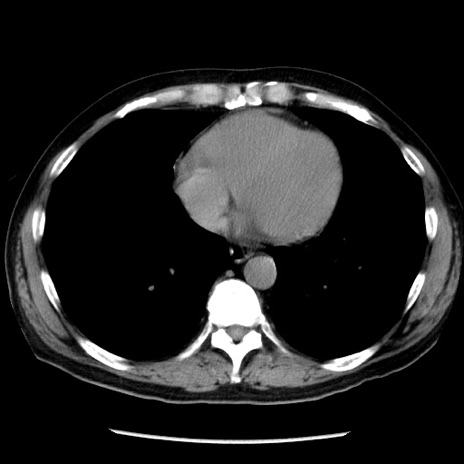

冠状断像

【症例】40歳代男性

【現病歴】2日前から胃痛あり。徐々に周期的な激痛に変化した。本日になっても激痛があるため受診。

【身体所見】意識清明、BT 38-39℃台あり、腹部:膨満、やや硬、右下腹部に圧痛あり。

【データ】WBC 8500、CRP 23.26